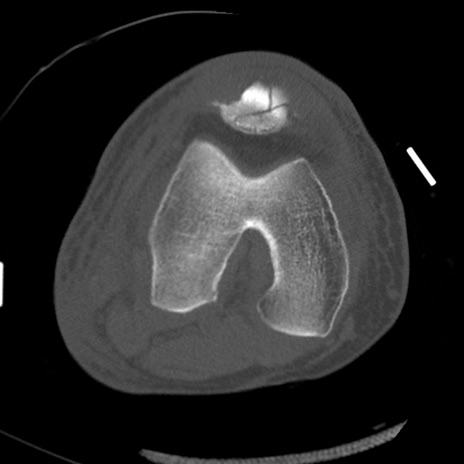

症例28 右膝関節CT(横断像)

右膝関節CT